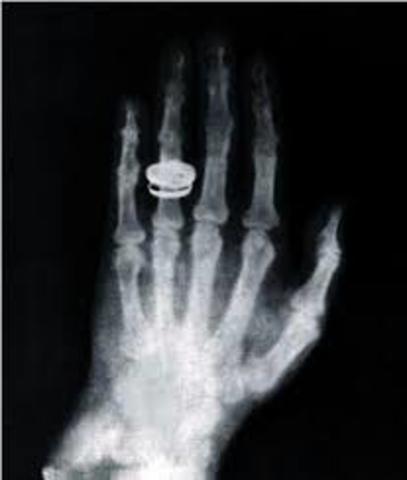

Primera Radiografía

Wilhelm aplico los efectos de los rayos x a la mano de su esposa lo cual nos dio la primera radiografía de la humanidad.